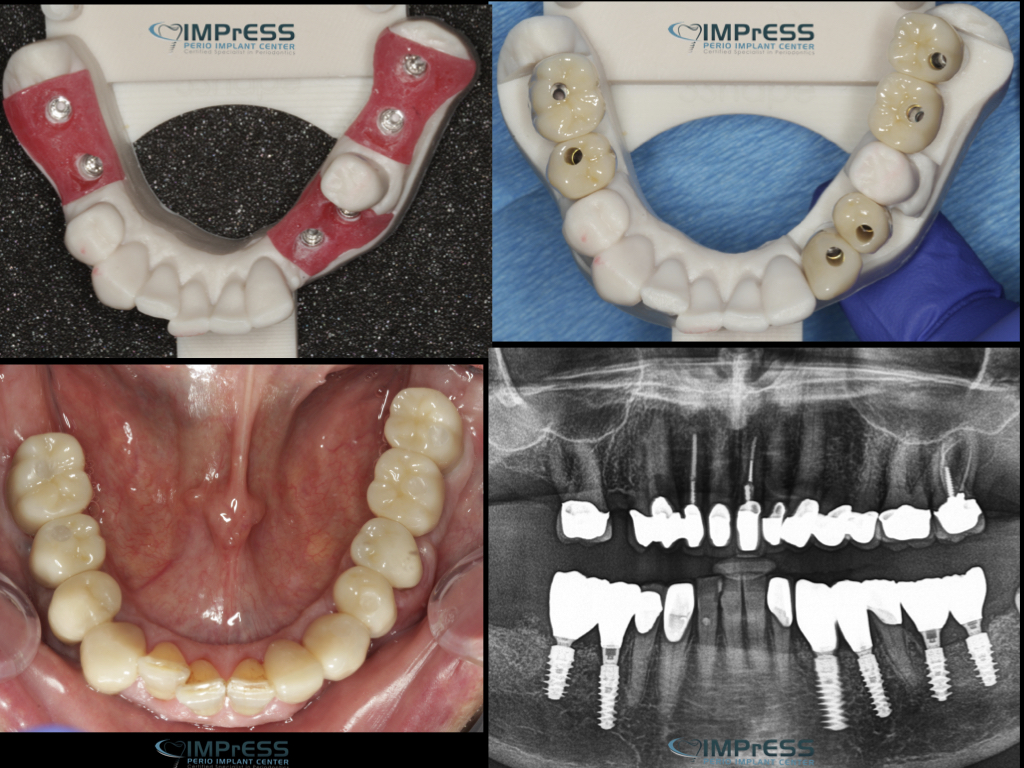

Before & Afters of Dental Implant Patients

Complete Dental Implant Cases Gallery

Dental implant treatment is sometimes a team effort between your periodontist and a restorative dentist.  Dr. Noroozi  at IMPrESS Perio Implant Center located in Burnaby BC performs the actual implant surgery, initial tooth extractions, and bone and gum grafting if necessary.  The restorative dentist (your dentist) or our specialists (if you do not have a dentist) will fit and make the permanent prosthesis. Your dentist or our specialists will also make any temporary prosthesis needed during the implant process.

General Disclaimer: The results in the photographs are examples only and do not imply any certainty of the result of a procedure, and all outcomes are subject to the circumstances of the individual patient.